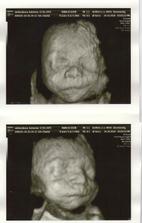

3D - nas poklad

Nas drobcek na 3D

bolo to teraz v nedelu 24.10 a bola som 22 tyzden 5 den.Ale mala je o tyzden popredu tak podla merania lekara bola 23 tyzden 5 den